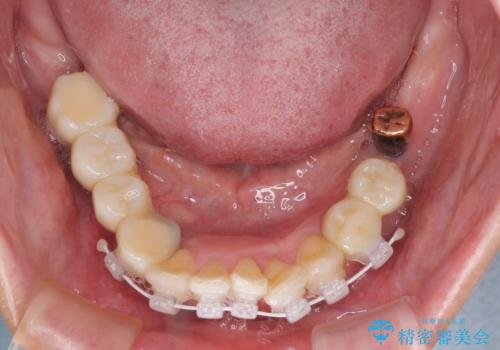

- 歯周病を放置したことで奥歯が抜け、前歯も痛くなってきたとのことで来院された患者様です。

奥歯はほとんどを抜歯しなければならない状態であり、抜歯をせずに済む歯も歯周外科処置や矯正治療を行う必要がある状態でした。

歯を抜かないといけない部分はインプラントとオールセラミッククラウンにより咬合を回復させ、歯周外科処置を行う歯については、同じくオールセラミッククラウンにて補綴治療を行うこととしました。

外科処置を多く行ったため、その待ち時間が長くかかり、さらには途中矯正治療も行なったので、治療期間は長期間となりました。